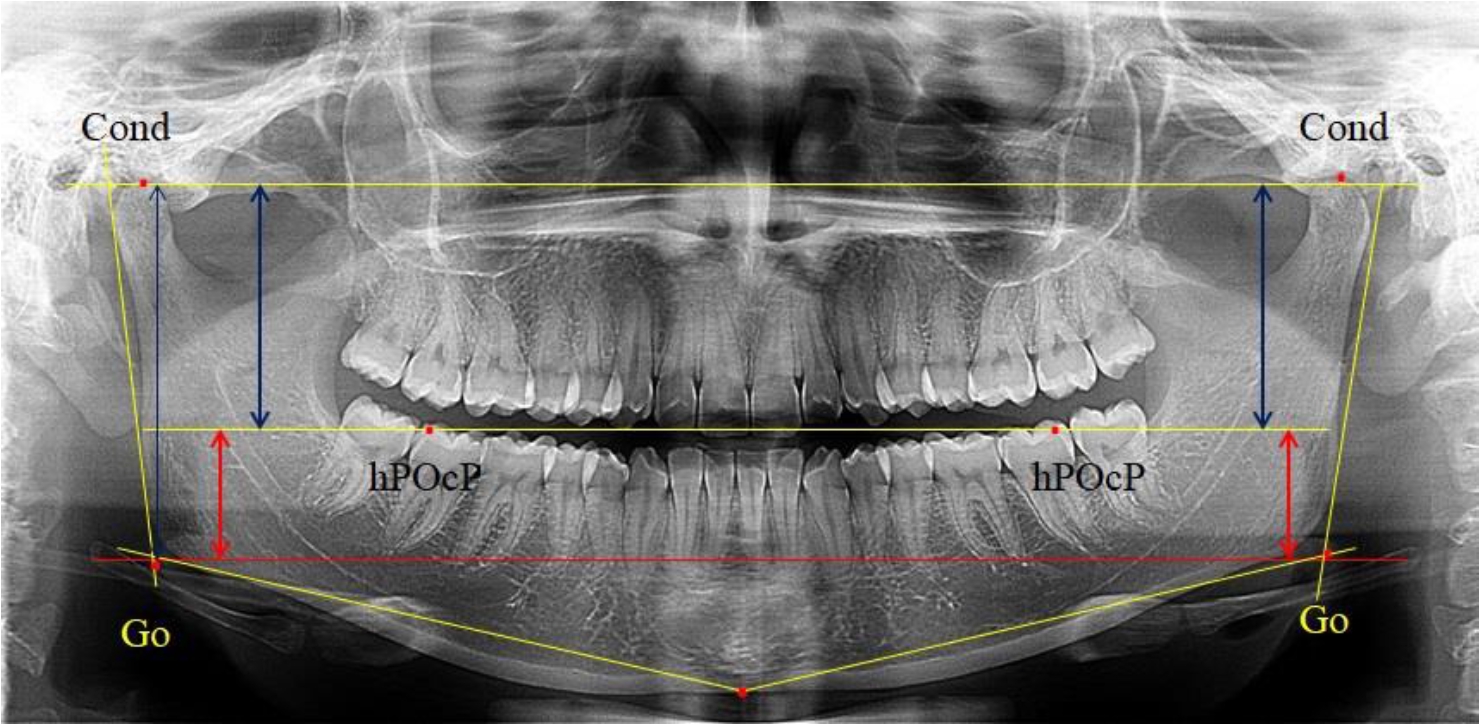

3-я подгруппа была с наименьшим количеством анализируемого материала, и здесь было проанализировано 17 комплектов рентгенограмм [(22,97 ± 4,89) %], на которых средняя величина отношения верхней части ветви к нижней составляла 2,45 ± 0,04, что было достоверно больше показателя, полученного по группе в среднем, а также в 1-й и 2-й подгруппе. Визуально параметры ветви отличались от других подгрупп. Высота ветви составляла (57,83 ± 0,89) мм, что было несколько меньше, чем в других подгруппах. Максимальная высота была 64 мм, а минимальная – 53 мм. Высота верхней части составляла (41,03 ± 0,59) мм, что было близким по значениям, полученным в других подгруппах и свидетельствовало о меньшей вариабельности указанного параметра. В то же время высота нижнего отдела ветви была (16,83 ± 0,36) мм и показатель отличался в меньшую сторону, по сравнению с аналогичным размеров в других подгруппах (рис. 4).

Рис. 4. ОПТГ пациента 3-й группы с увеличенным коэффициентом соотношения частей ветви нижней челюсти